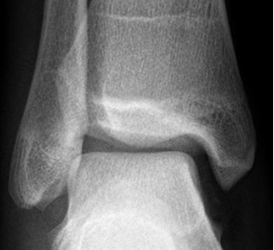

Las lesiones crónicas producen irregularidad, engrosamiento o alargamiento del ligamento y disminución de la grasa vecina por fibrosis o proliferación sinovial. (1). Estos cambios crónicos serán revisados mas ampliamente, en los síndromes de pinzamiento. (Fig 65 y 66).

Fig 66. Lesión ligamentaria crónica.

A: Rx AP. Calcificación en el borde inferior del maléolo interno y prominencia de los tejidos blandos.

B: RM coronal en STIR y C: RM axial en T2. Engrosamiento del ligamento tibiocalcáneo (Flechas), por lesión crónica, sin signos de ruptura completa.